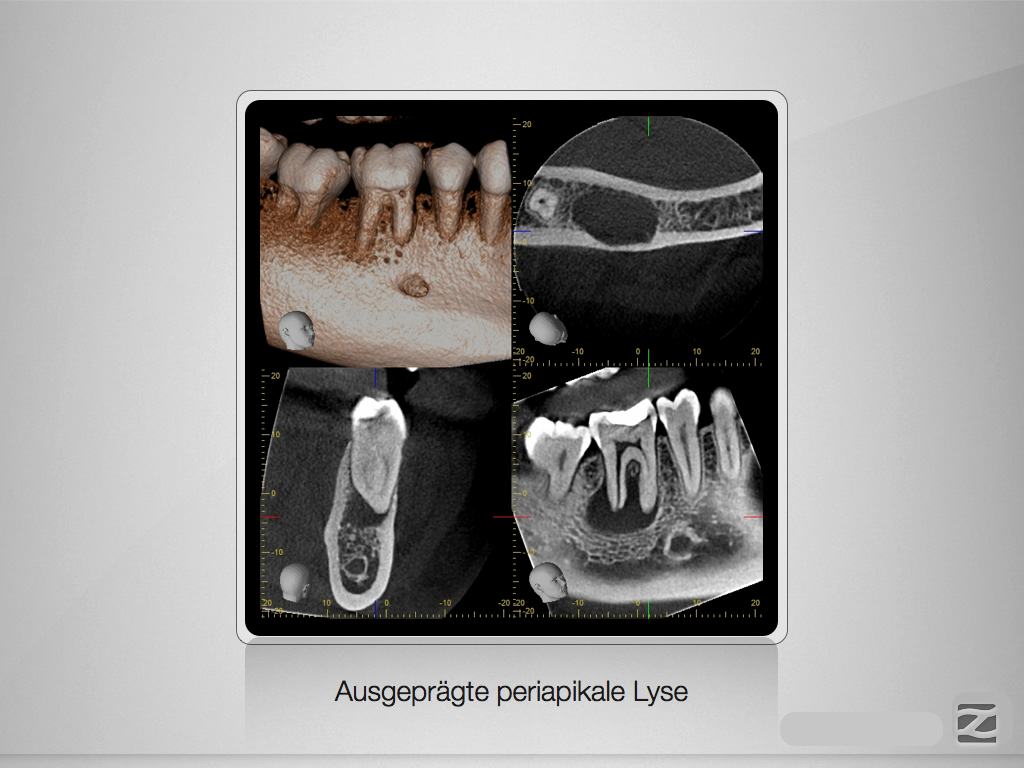

46D.002

Therapieplanung nach DVT